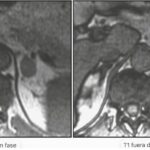

La resonancia magnética

La resonancia magnética es una modalidad de imagen basada en radiación no ionizante que utiliza señales débiles de onda de radio emitidas por los tejidos del cuerpo cuando el cuerpo se coloca en un campo magnético fuerte y se aplican pulsos de radiofrecuencia. Las ventajas de la resonancia magnética sobre la TC son su falta de exposición a la radiación, la falta de medios de contraste a base de yodo y su resolución de contraste tisular superior. Los tiempos de escaneo más largos, la claustrofobia y los dispositivos incompatibles con la resonancia magnética in situ son las principales desventajas de esta. Para la diferenciación de las masas suprarrenales benignas y malignas, la técnica de resonancia magnética de la imagen de desplazamiento químico se utiliza más comúnmente. La imagen de desplazamiento químico se basa en el hecho de que, dentro de los campos magnéticos, los protones en el agua vibran a una frecuencia ligeramente diferente a la de los protones en los lípidos. Como resultado, el agua y los protones de grasa oscilan dentro y fuera de fase entre sí.

Los adenomas suprarrenales con un alto contenido de lípido intracelular generalmente pierden intensidad de la señal en las imágenes fuera de fase en comparación con las imágenes en fase, mientras que las lesiones malignas y los feocromocitomas (pero también algunos adenomas suprarrenales pobres en lípidos) que carecen de lípido intracelular permanecen sin cambios y conservan su señal.(22)

Las unidades de intensidad de la señal de RM son unidades arbitrarias, a diferencia de la TC, y por lo tanto están sujetas a numerosas variaciones técnicas. La evaluación visual simple de la pérdida de intensidad de la señal es diagnóstica en la mayoría de los casos, reservando los métodos cuantitativos a casos menos claros. Las directrices más recientes sugieren que la evaluación de la resonancia magnética de las lesiones suprarrenales debe usarse principalmente como una herramienta de resolución de problemas.

La resonancia magnética con imágenes de cambio químico solo debería ser la primera opción donde la TC es menos deseable, por ejemplo, durante el embarazo, en niños o para pacientes con alergias al contraste yodado.(23)

El uso de la resonancia magnética de desplazamiento químico para detectar grasa intracelular dentro de adenomas suprarrenales ricos en lípidos y diferenciarlas de otras lesiones se describió por primera vez en 1992.

Hay métodos cualitativos (análisis visual) y cuantitativos de evaluación de imágenes que implican la evaluación del cambio en la intensidad de la señal de las lesiones suprarrenales entre secuencias en fase y fuera de fase.(24)

Una revisión sistemática reciente y un metaanálisis informaron que el análisis visual y el análisis cuantitativo del índice de intensidad de la señal suprarrenal y la relación suprarrenal-bajo tienen una alta precisión para la detección de adenoma rico en lípidos (95%-98%), y el rendimiento diagnóstico no mejora significativamente por el índice de intensidad de la señal suprarrenal o la relación suprarrenal a bajo(24) (Figura 2). En consecuencia, si se detectan IA en la resonancia magnética y los hallazgos son inequívocos para un adenoma benigno rico en lípidos, es posible que no se justifiquen más imágenes.